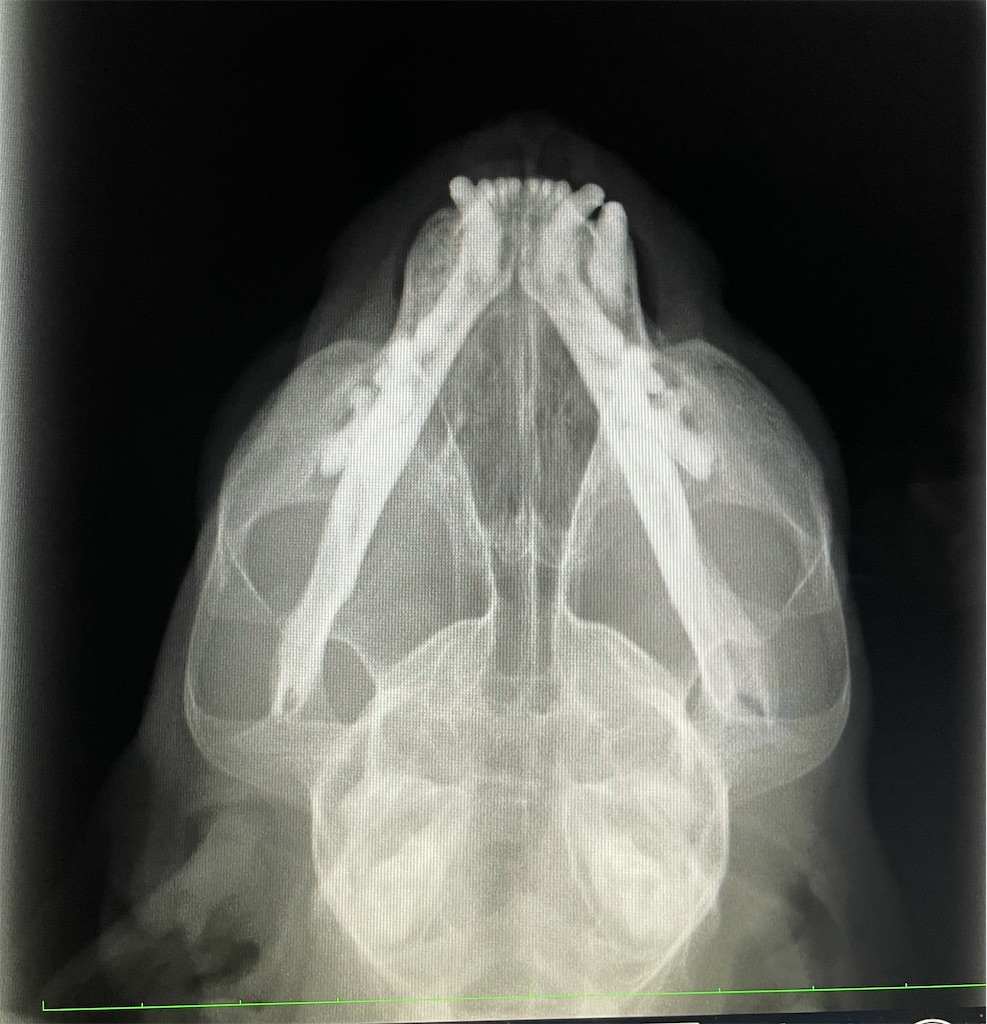

▪肺のレントゲン経過観察結果▪

残念ですが肺の結節が少し大きくなっていました。。。現在約1.2㎜程度。

発見時からほんの少しづつですが、大きくなっている感じです。次回のレントゲンでさらに大きくなる様だったら生検か、再度麻酔をかけてCTか。。。また悩ましい状態となりました。万が一悪性だった場合、など様々なパターンでの今後の説明を受けましたが、現段階では楽観的に捉えていたいと思っています。

結論から書くと、レントゲンで確認して頂いたところ、「絶対」とは言えないものの、怪しい影(腫瘍)は見当たらずおそらく持病の慢性副鼻腔炎で粘膜(毛細血管)が傷ついた事によるものであろうとの事でひと安心。

のんちゃんはレントゲン耐えて頑張っていたそうです。それにしても、透け透けのんちゃんもかわいい。